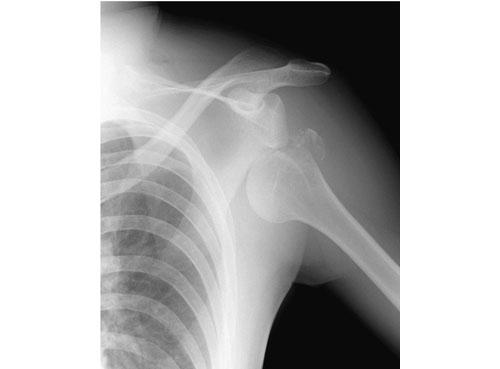

7

理学療法士実地問題 -

第52回 午前

重要度:標準

30歳の男性。スキーで転倒して受傷した。エックス線写真を示す。肩脱臼整復後に肩関節内転・内旋位で固定されたが、上腕の外側上部に感覚鈍麻を訴えた。合併症の神経麻痺はどれか。

1

腋窩神経

2

肩甲上神経

3

肩甲下神経

4

尺骨神経

5

正中神経